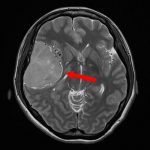

手術前1

手術前2